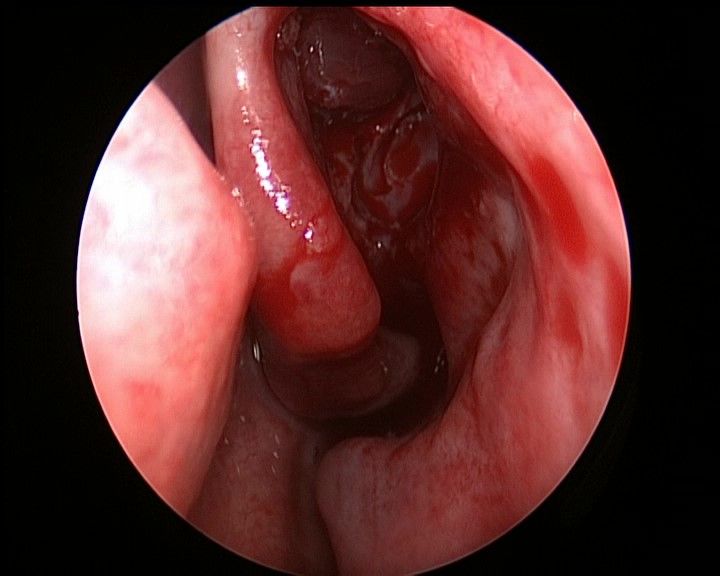

抵近观察左侧右鼻孔 ↓

↑ 去除左侧中鼻甲,抵近观察左侧蝶筛隐窝